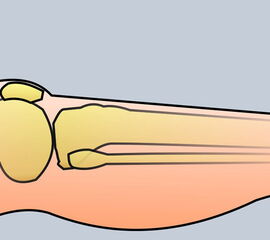

Exzision des Endglieds unter Bildung eines plantaren Lappens (Abb. 4). Die Absetzung kann im Endglied, im Endgelenk als Exartikulation oder im Grundglied distal der Ansätze der kurzen Beuger vorgenommen werden. Der Verschluss der Wunde durch Nähte ist wegen des längeren plantaren Lappens meist nur „mokassinartig“ möglich. Die Unregelmäßigkeiten werden im Verlauf der Wundheilung spontan ausgeglichen (Abb. 5).